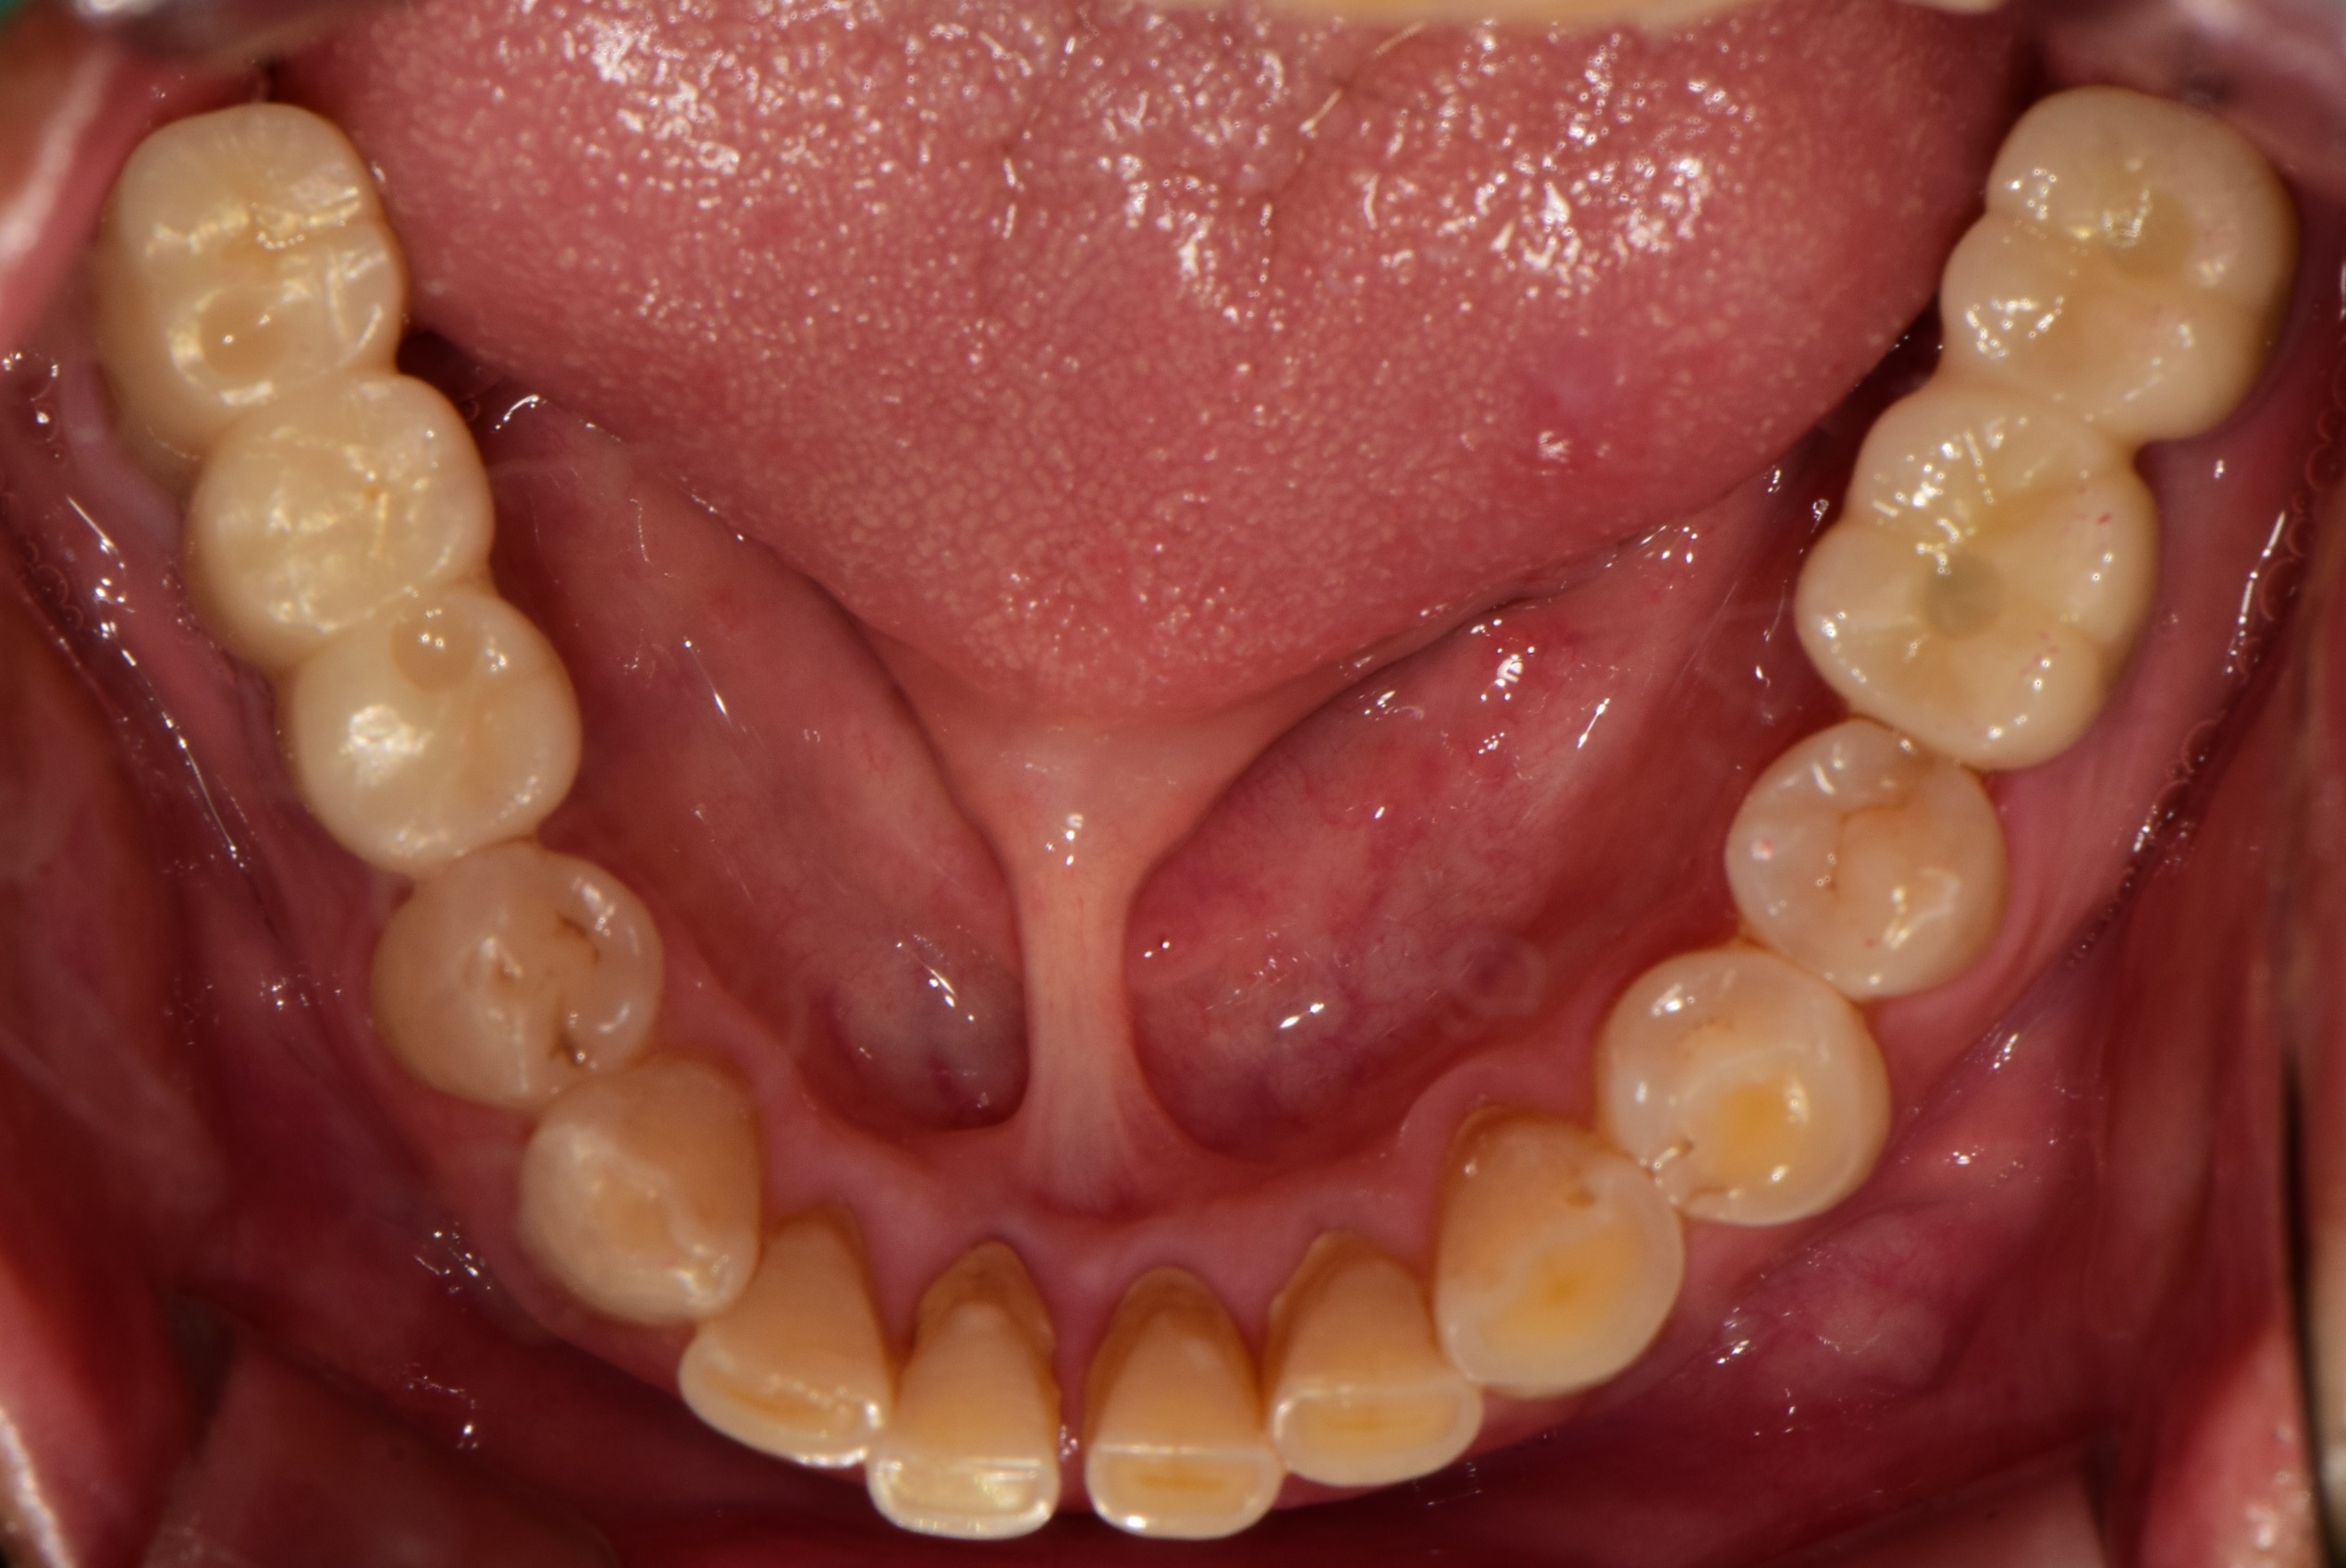

오랜기간 어금니가 없이 지내셨던 60대 남성분의 치료 사례입니다.

처음 김포 치과에 내원하셨을 당시 위에는 송곳니 하나를 제외하고는 다 흔들리고 어금니는 빠진지 오랜된 상태였습니다.

위턱에는 8개의 임플란트를 식립하여 전체 치아를 수복해드렸고,

아래턱은 4개의 임플란트를 식립하여 어금니를 수복해 드렸습니다.

<치료 전>

<치료 후>